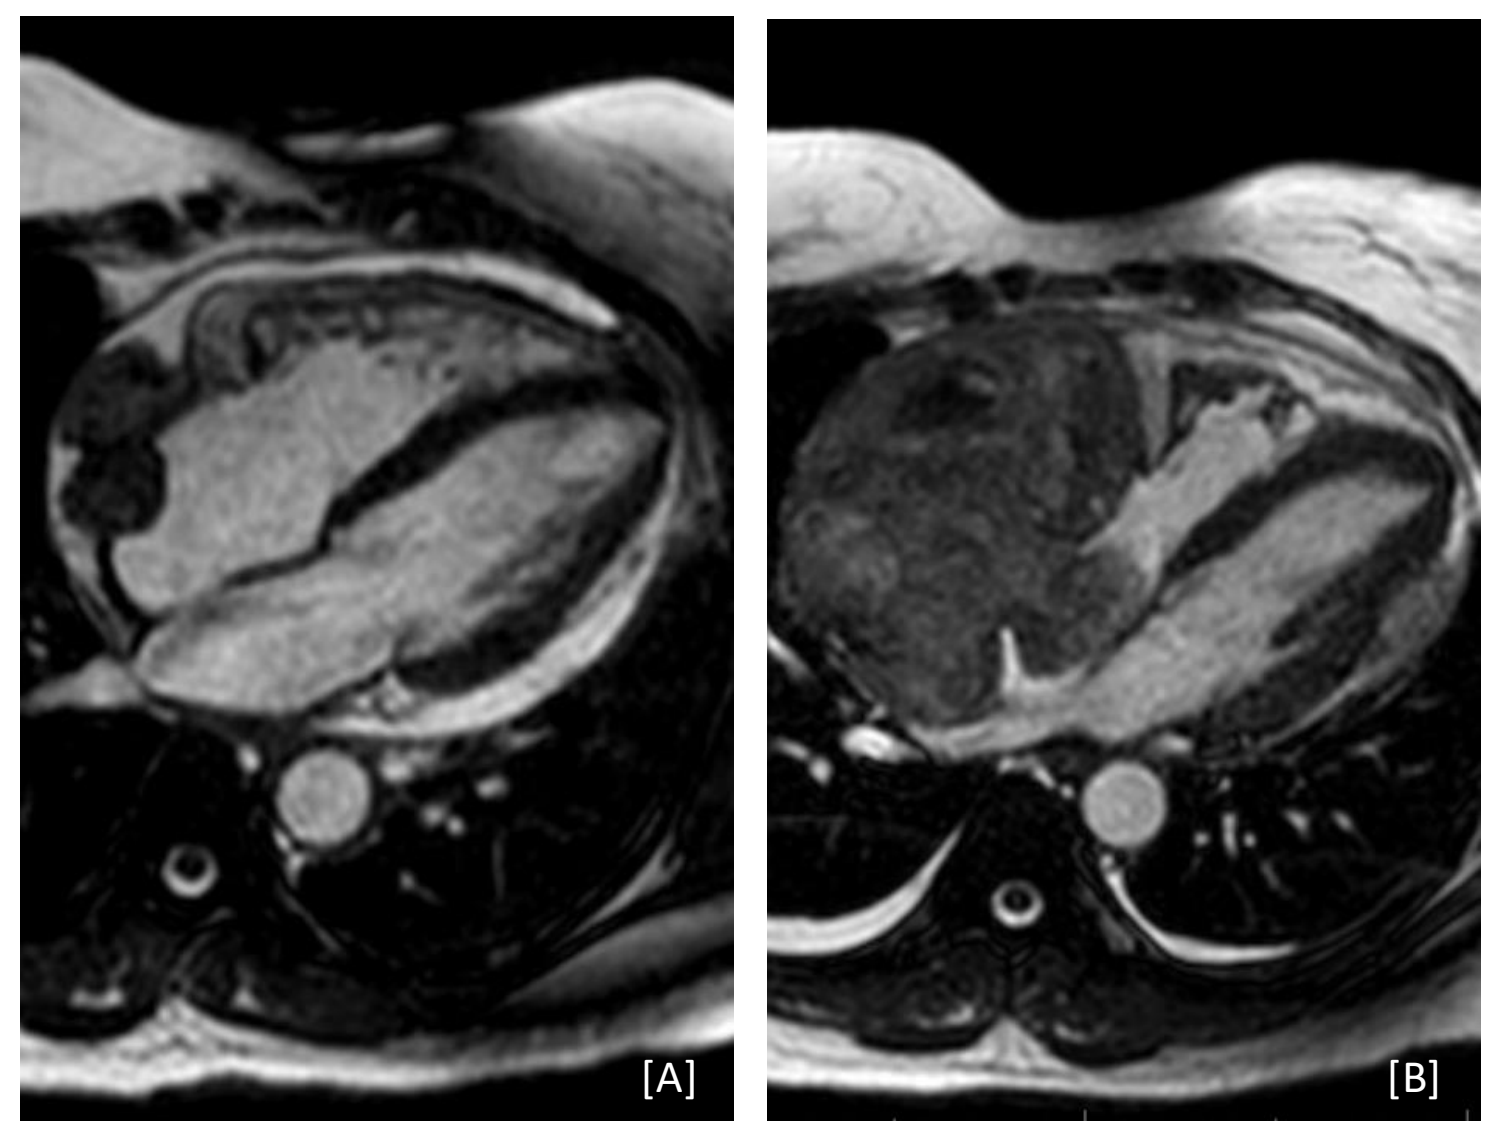

Case Presentation: A 53-year-old female with history of two recent admissions for idiopathic pericarditis presented with several days of increasing chest pain, dyspnea, and lightheadedness. During her first admission three months prior, she underwent urgent pericardiocentesis with pericardial drain placement for early cardiac tamponade. Fluid cytology results were unremarkable. Cardiac computed tomography demonstrated a focal, lobulated contour change of the right atrium initially attributed to post-operative change. Transthoracic echocardiography and cardiac magnetic resonance imaging (MRI) demonstrated a 2.4 x 2.0cm well-circumscribed, lobulated mass thought to be thrombus or hematoma after discussion with cardiology and cardiothoracic surgery. She was discharged with ibuprofen and colchicine with plans to repeat imaging in several weeks. She was briefly readmitted four days later with similar symptoms found to have atrial flutter with rapid ventricular response. She responded well to amiodarone and discharged on a taper, which she finished by the time of current admission.On presentation, she was hemodynamically stable with labs notable for leukocytosis (14.3 x 10^9/L white blood cells) and elevated C-reactive protein (18 mg/L, decreased from a peak of 128 mg/L in her first admission). Repeat cardiac MRI discovered significant growth of the mass to 11.6 x 7.7cm, with a contiguous portion projecting into the right atrium. A separate mass was also found on the left atrial wall measuring 2.0 x 2.9cm with evidence of vascularity. Biopsy of the mass confirmed high grade angiosarcoma. Due to high surgical risk, resection was not undertaken and initial neoadjuvant chemotherapy was recommended instead. Chemotherapy with gemcitabine and docetaxel was initiated several days after discharge. However, the tumor continued to progress through chemotherapy and metastasized to her right femur 3.5 months after initial presentation. Unfortunately, she expired two months later.